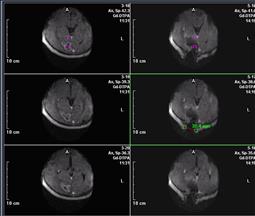

ODTÜ Deniz Bilimleri Enstitüsü ile Gıda, Tarım ve Hayvancılık Bakanlığı Trabzon Su Ürünleri Merkez Araştırma Enstitüsü (SUMAE) işbirliğinde Karadeniz'deki hamsi stoğunu belirlemek üzere başlatılan bilimsel projenin ilk sonuçları alınmaya başlandı. Buna göre, denizde yapılan akustik taramalardan elde edilen bulgular, yeni av sezonunda hamsi avcılık düzenlemeleri için analiz edildi, hamsinin kışlama alanları 3 boyutlu haritalandı.